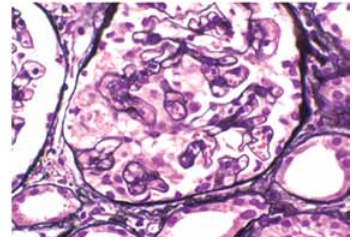

Paciente feminina, 31 anos, com queixas de faringoalgia e febre, recebeu prescrição de penicilina benzatina, com resolução de quadro clínico. Cinco dias depois, iniciou cefaleia frontal, indisposição e notou diminuição do volume urinário, com aspecto mais nublado da urina. Refere edema discreto e nega tanto hipertensão neste período quanto doenças prévias. Procurou o pronto atendimento, onde foi verificada piora de função renal (creatinina de 3,5 mg/dL), hematúria, leucocitúria e proteinuria +++/4 em fita de urina.

Submetida à biópsia renal: cortical representada por 28 glomérulos, 15 glomérulos apresentam hiperplasia podocitária segmentar e colapso parcial ou global de alças capilares. O restante deles tem a estrutura geral preservada, com celularidade normal, capilares com luz patente e membrana basal sem alterações significativas. As cápsulas de Bowman estão íntegras.

(Coloração de prata de Jones. Disponível em: https://www.ajkd.org)

A opção diagnóstica que melhor justifica o caso é: